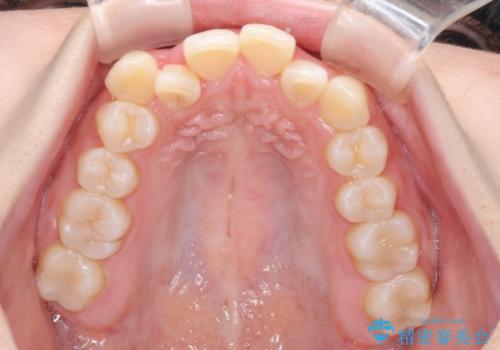

- 上顎の八重歯と、上下前歯のデコボコを気にして来院された患者様です。

奥歯の咬み合わせを見ると、上顎臼歯が下顎に対して前方にあり、叢生改善により口元が突出する顔貌ではなかったため、上顎左右第一小臼歯2本を抜歯し、ワイヤー装置にて矯正治療を行うこととしました。

前歯部のデコボコがなくなったため、歯磨きしやすくなり、非常に清潔な状態になりました。